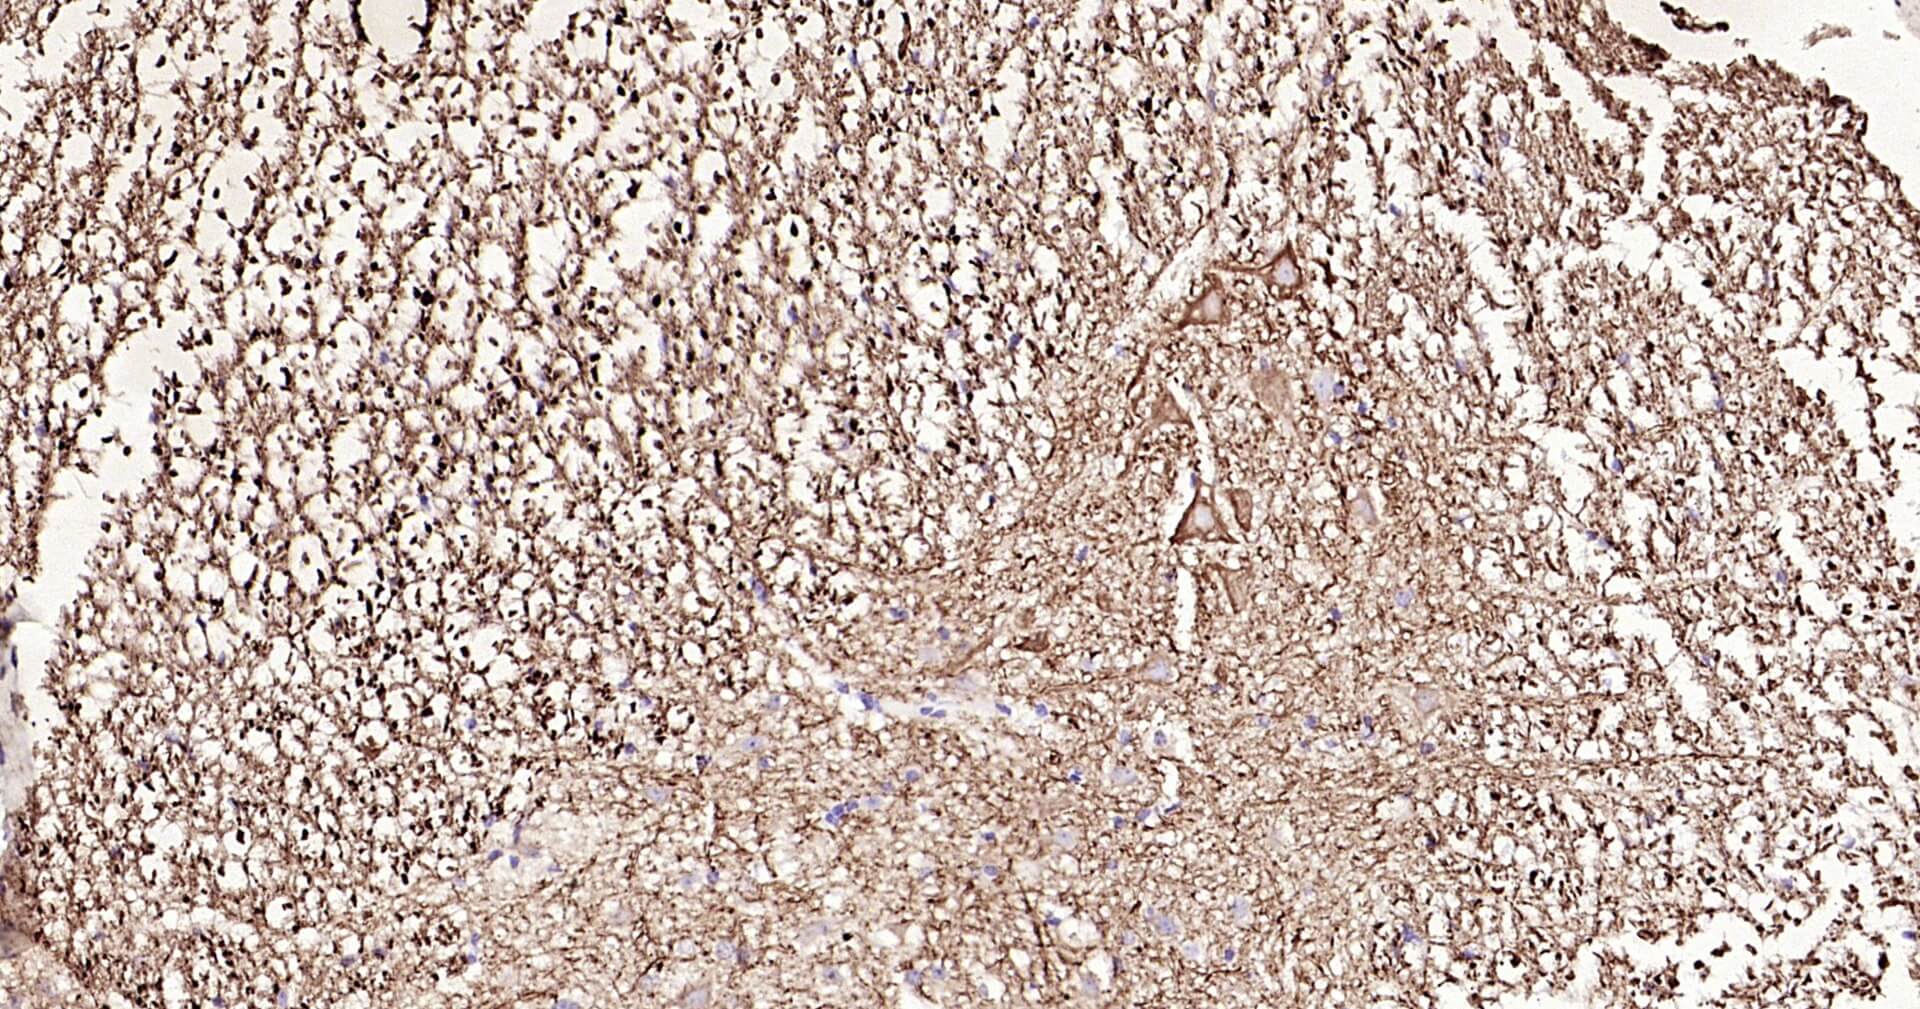

Immunohistochemical analysis of paraffin embedded mouse spinal cord tissue slide using IHC0129 (NF-L IHC Kit).

Immunohistochemical analysis of paraffin embedded mouse cerebellum tissue slide using IHC0129 (NF-L IHC Kit).

Immunohistochemical analysis of paraffin embedded rat spinal cord tissue slide using IHC0129 (NF-L IHC Kit).

Immunohistochemical analysis of paraffin embedded rat cerebellum tissue slide using IHC0129 (NF-L IHC Kit).

Immunohistochemical analysis of paraffin embedded human cerebellum tissue slide using IHC0129 (NF-L IHC Kit).